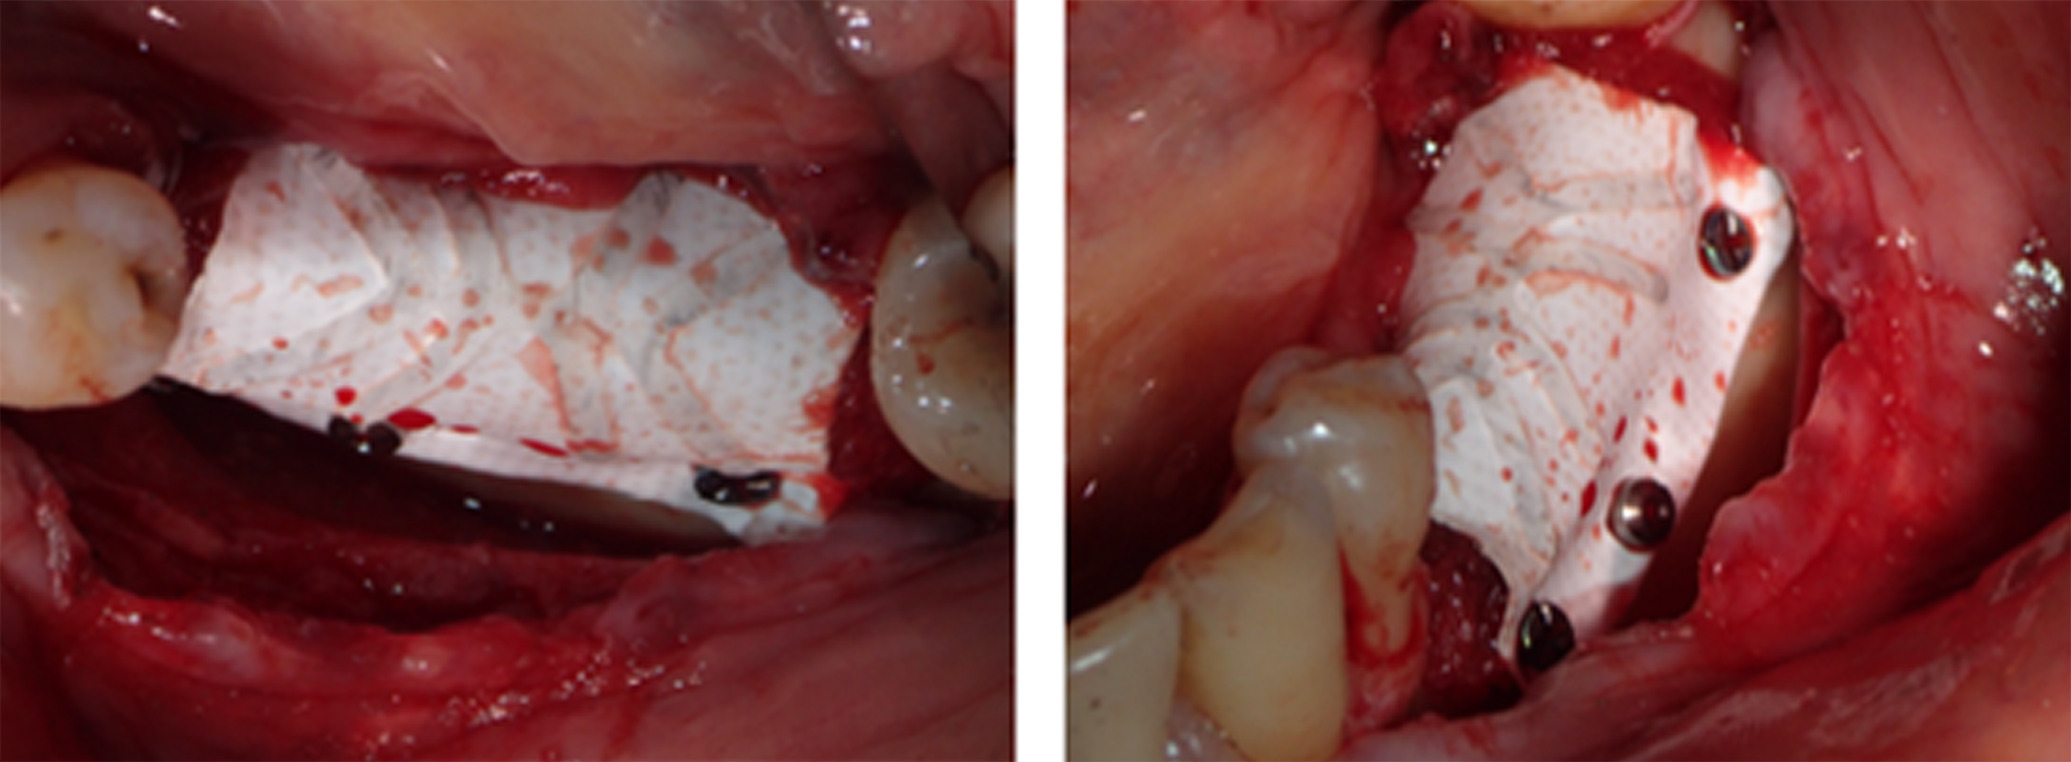

Next, buccal and lingual reaming was carried out to ensure bleeding and adequate irrigation of the bone graft (Figure 5). GBR was facilitated first through a combination of autograft obtained from the mandibular ramus using a SafeScraper® (META; Reggio Emilia, Italy) and C/C Mix (Figure 6). Then, an outer layer of F-DBM was added for extra volume and to contain the underlying particulate (Figure 7). To maintain stability of the bone graft, a Cytoplast dense titanium-reinforced PTFE membrane (Osteogenics; Lubbock TX, USA) was fixed with buccal and lingual pins (Figure 8). Finally, an outer layer of bovine pericardial membrane (Nobel Biocare, Kloten, Switzerland) was placed to provide a bilayer of interlaced, multidirectional Type 1 collagen fibers (Figure 9). A combination of horizontal mattress and simple sutures with nonresorbable Cytoplast PTFE 3.0 monofilament (Osteogenics) were then used to provide optimal closure of the flap without tension. Perioperative computed tomography (CT) scans confirmed pin and titanium-reinforced placement but, characteristic of regenerative materials, bone particulate and fibers were not radiopaque (Figure 10).

Figure 8. To maintain stability of the bone graft, a Cytoplast dense titanium-reinforced PTFE membrane was fixed with buccal and lingual pins

Figure 9. An outer layer of bovine pericardial membrane was placed to provide a bilayer of interlaced, multidirectional Type 1 collagen fibers